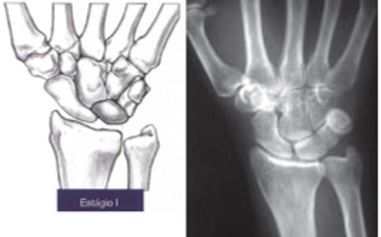

Como é o estágio I de Lichtman

A

• Rx normal

ou

• Fratura Linear

• Hipo em T1 e T2 na RM